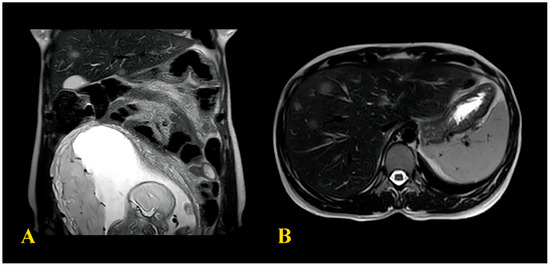

2.2. Case Report 2